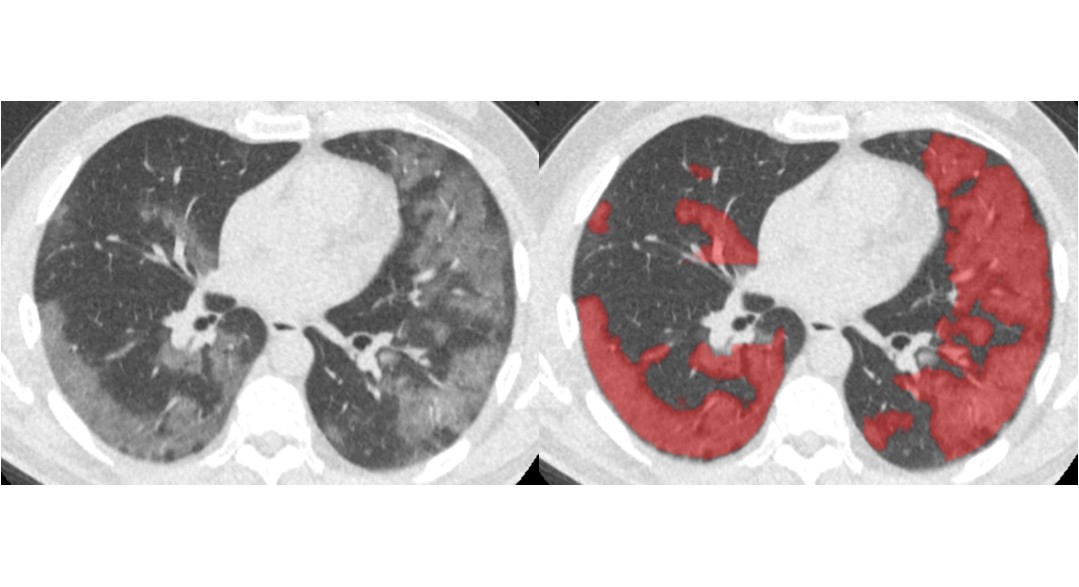

Thirona developed an AI algorithm that revolutionizes cystic fibrosis (CF) care.